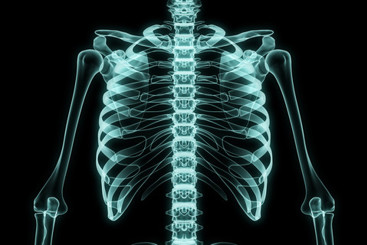

• Grafikk - Røngtenbilde av overkropp hentet fra colourbox.com